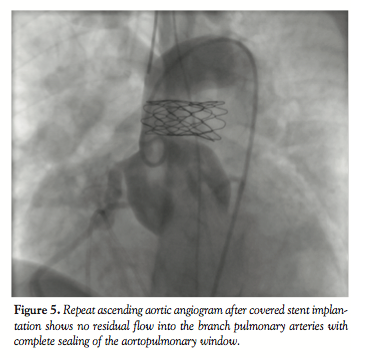

further delineate the anatomy. Ascending aortic angiogram showed significant opacification of the PAs (Figure 3). The aortopulmonary window could be crossed easily from the PA into the aorta by advancing a wedge catheter with the balloon inflated; hence, its diameter was above 1 cm. It was decided not to balloon-size the defect, because of the possibility of further increasing its size. Therefore, a 34-mm long covered stent that was premounted on a 16-mm diameter balloon was chosen and implanted at the exact point of the window, sealing it off and at the same time relieving the left PA stenosis (Figures 4 and 5).